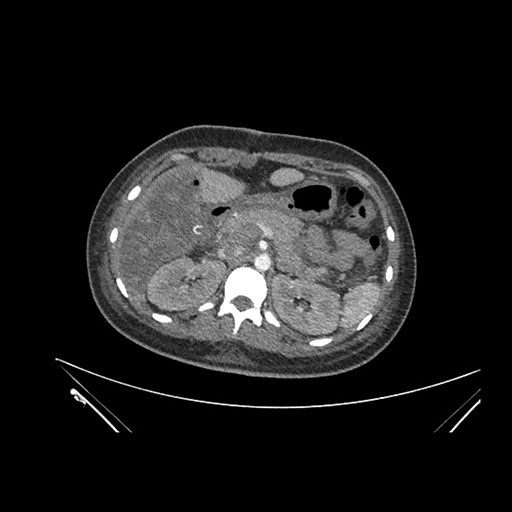

Imaging Analysis

Look through the patient's CT scan to identify any areas of concern for the necessary procedure.

Axial Venous

Based on initial findings, which issue(s) would you be most concerned about?